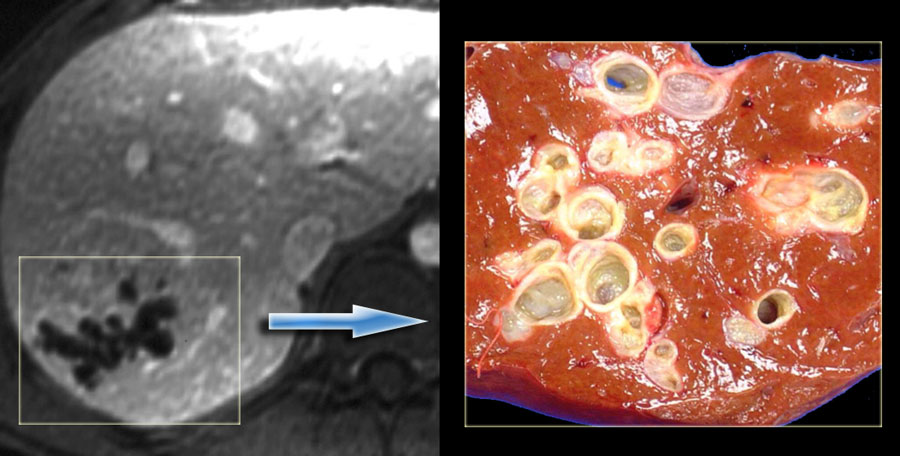

Artigo atualizado: doença e síndrome de Caroli

Descrita pela primeira vez por Jacques Caroli em 1958, é uma doença genética rara. A forma mais simples, chamada de doença de Caroli, é caracterizada como dilatação dos dutos biliares principais (maiores), sem obstrução, que podem permanecer assintomáticas até a idade adulta, e ocorre esporadicamente (sem uma […]